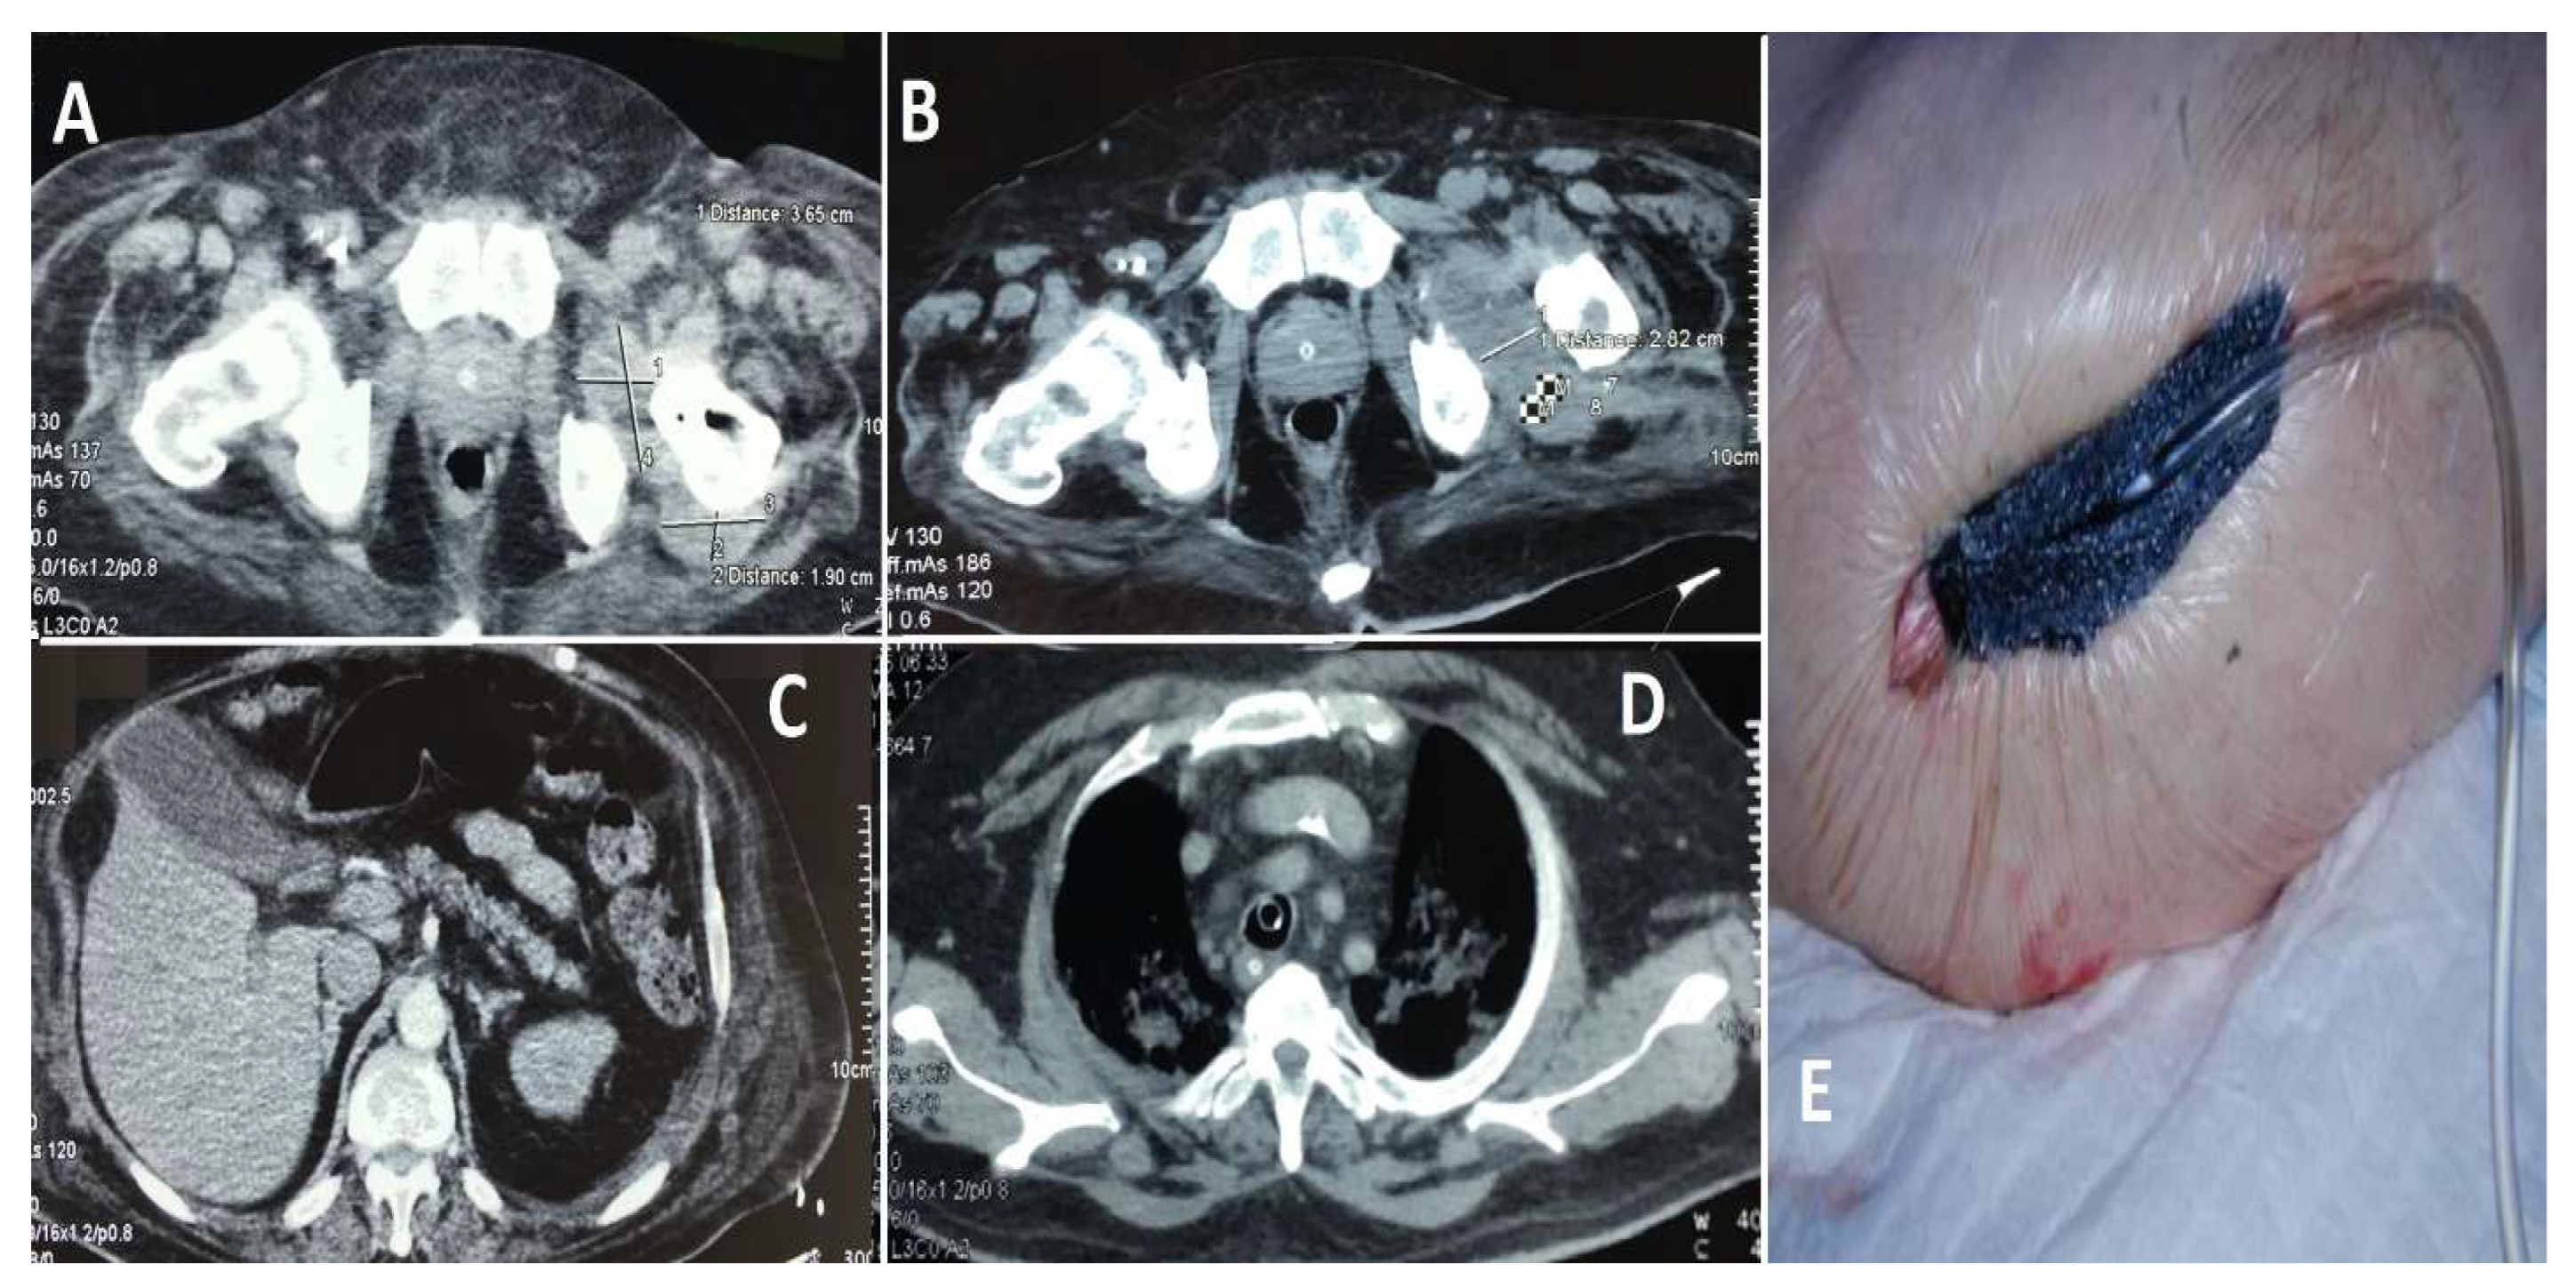

Case 1 (see Figure 6): A 67-year-old male with multiple comorbidities, including chronic renal failure, morbid obesity, diabetes mellitus, chronic heart failure, two coronary stents, and atrial fibrillation necessitating long-term anticoagulation therapy, presented with a septic infection of a hip prosthesis implanted approximately 10 years prior. The patient’s substantial comorbidities had a significant impact on both the surgical procedure and subsequent care. During his hospitalization, the patient displayed electrocardiogram (ECG) alterations suggestive of an ST-elevation myocardial infarction (STEMI) in the inferolateral region. Subsequent diagnostic assessments, including transesophageal echocardiography, identified the presence of vegetation on the aortic valve, indicative of endocarditis. The initial decision was to defer the planned cardiovascular surgery due to the patient’s rapidly deteriorating general condition and precarious health status. Instead, broad-spectrum antibiotics were provided. Following a two-week course of antibiotic treatment, the patient experienced a spontaneous splenic rupture, necessitating an emergency splenectomy; the patient’s condition continued to deteriorate. A subsequent transesophageal ultrasound revealed further expansion of the valvular vegetations, necessitating immediate valvuloplasty. The procedure was completed successfully, and the patient was initiated on a robust anticoagulant regimen postoperatively. A computed tomography (CT) scan of the hip revealed the presence of periprosthetic collections, thereby confirming the persistence of the local infection. A revision arthroplasty was performed, during which a cemented prosthesis was inserted to replace the contaminated hardware. Despite these interventions, the patient’s general health continued to deteriorate due to the complexity of his medical condition and the persistence of the infection. Despite comprehensive antibiotic therapy, surgical procedures, and intensive care support, the patient experienced multi-organ failure and ultimately succumbed to their illness after approximately six weeks of treatment.

Figure 6. Images (A,B): The presence of a notable fluid collection in the hip region suggests the possibility of a periprosthetic infection. The presence of this accumulation was a crucial factor in the diagnosis of the infection. Image (C): A splenic lesion is observed, necessitating a splenectomy due to spontaneous rupture resulting from infectious complications. Image (D): The presence of valve vegetations on the aortic valve necessitates the performance of a valvuloplasty. The vegetations were identified through the utilization of transesophageal echocardiography, a diagnostic technique employed to assess the patient’s condition. Image (E) depicts the postoperative status of the hip, which has been fitted with a negative pressure drainage device to facilitate wound healing and reduce the accumulation of contaminated fluid.